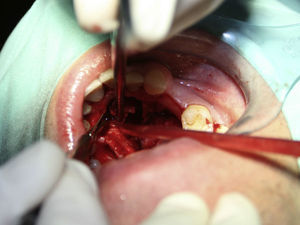

Case reportA case of a nasopalatine duct cyst in a 45-year-old male is presented (Fig. 1). The patient was referred, reporting a pressure over the anterior maxilla. There were no other symptoms and no recent history of pain. Clinical examination revealed a palatal expansion on the anterior hard palate (Fig. 2). There was no previous history of trauma. The patient was asked to take a computerized axial tomography which showed a well-defined radiolucency in the anterior maxilla in the region of incisive canal (Fig. 3). Loss of cortical bone was seen along the palatal aspect of the lesion in the sagittal sections (Fig. 4). Also resorption of nasal cavity floor bone could be seen in those sections. The cyst was enucleated under general anaesthesia. A palatal mucoperiosteal flap was raised and following bone removal, the friable, haemorrhagic cyst lining was curetted and sent for histological examination fixed in 10% neutral formalin (Figs. 5 and 6). After cyst removal it could be seen in the depth of surgical loca a small communication with the nasal cavity. Gross examination revealed a whitish, soft consistency fragment measuring 2.2cm×1.5cm×0.4cm (Fig. 7). Microscopic examination revealed fibrous wall lined by thin stratified squamous epithelium without inflammatory infiltrate and with some clear cells of ciliated appearance, which confirms the diagnosis of nasopalatine duct cyst (Fig. 8). The patient showed no clinical or radiographic signs of recurrence one year after surgical excision (Fig. 9).